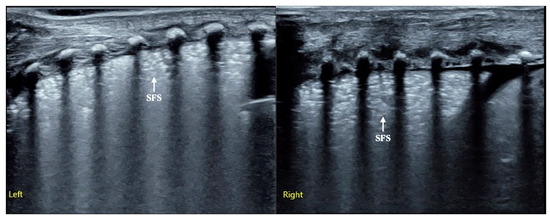

The Outcome- or Cost-Effectiveness Analysis of LUS-Based Care or CXR-Based Care of Neonatal Lung Diseases: The Clinical Practice Evidence from a Level Ⅲ NICU in China

by Jing Liu, Xin Zhang, Yan Wang, Jie Li, Wei Yan, Sheng-Juan Qin, Xiao-Ling Ren and Wei Fu

Objective: To compare the effect of managing neonatal lung disease with lung ultrasound (LUS) or chest X-ray (CXR) monitoring on health outcomes and cost-effectiveness. Methods: The data obtained from the NICU of the Beijing Chaoyang District Maternal and Child Healthcare Hospital were used [...] Read more.

Objective: To compare the effect of managing neonatal lung disease with lung ultrasound (LUS) or chest X-ray (CXR) monitoring on health outcomes and cost-effectiveness. Methods: The data obtained from the NICU of the Beijing Chaoyang District Maternal and Child Healthcare Hospital were used as the study group, as LUS has completely replaced CXR in managing newborn lung disease in the hospital for the past 5 years. The primary outcomes of this study were the misdiagnosis rate of respiratory distress syndrome (RDS), the using status of mechanical ventilation, the incidence rate of bronchopulmonary dysplasia (BPD) and the survival rate in hospitalized infants. The secondary outcomes included the use pulmonary surfactant (PS), and the mortality rate of severe diseases (such as pneumothorax, pulmonary hemorrhage and RDS, etc.). Results: Managing neonatal lung disease with LUS monitoring may enable the following effects: The frequency of ventilator use reducing by 40.2%; the duration of mechanical ventilation reducing by 67.5%; and the frequency of ventilator weaning failure being totally avoided. A misdiagnosis rate of 30% for RDS was also avoided. The dosage of PS was significantly reduced by 50% to 75%. No BPD occurred in the LUS-based care group for 5 years. The fatality rates of RDS, pneumothorax and pulmonary hemorrhage decreased by 100%. The poor prognosis rate of VLBW infants decreased by 85%, and the total mortality rate of hospitalized infants decreased by 90%. Therefore, the cost of LUS-based care was inevitably saved. Conclusions: Diagnosing and managing neonatal lung diseases with LUS monitoring have significant benefits, and this technology should be widely promoted and applied around the world. Full article